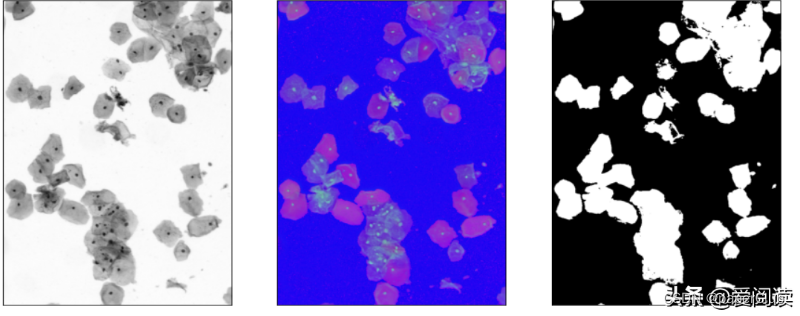

plt.subplot(131), plt.imshow(img_gray, 'gray'), plt.xticks([]), plt.yticks([])

plt.subplot(132), plt.imshow(img_hsv, 'gray'), plt.xticks([]), plt.yticks([])

plt.subplot(133), plt.imshow(bw_cell, 'gray'), plt.xticks([]), plt.yticks([])

细胞区域初步分割结果: